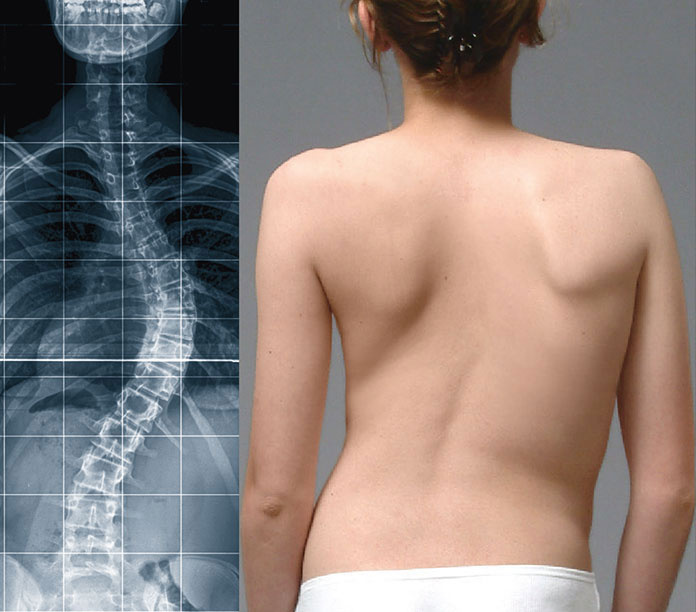

Welche sportarten bei skoliose vermeiden. Es gibt keine gesicherten Hinweise dafür dass bei vorbestehender Skoliose bestimmte Sportarten zu einer Zunahme der Deformität führen. Sportarten bei denen die Wirbelsäule großen Stoßbelastungen ausgesetzt ist sollten vermieden werden. Einige Skoliotiker bekommen Schmerzen bei starker Belastung da muss man auch ausprobieren was dir da gut tut und was nicht.

Bei Kindern und Jugendlichen ist eine Befreiung vom Schulsport bei leichten und mittelschweren Skoliosen nicht angezeigt. Bei Skoliosen bis zu 40 Grad sind generell alle Sportarten möglich und die aktive Teilnahme am Schulsport wird unbedingt empfohlen. Dies kann man mit einfachen Hantelübungen oder sogar ohne Gewichte durchführen.

Bezüglich der Neigung zu einem Rundrücken sind alle Sportarten geeignet die dafür sorgen dass Sie Ihr Atemvolumen steigern also Ausdauersportarten wie Rudern Schwimmen Radfahren. Sportarten bei denen die Wirbelsäule stark belastet wird wie beispielsweise Squash oder Kunstturnen sollten vermieden werden.